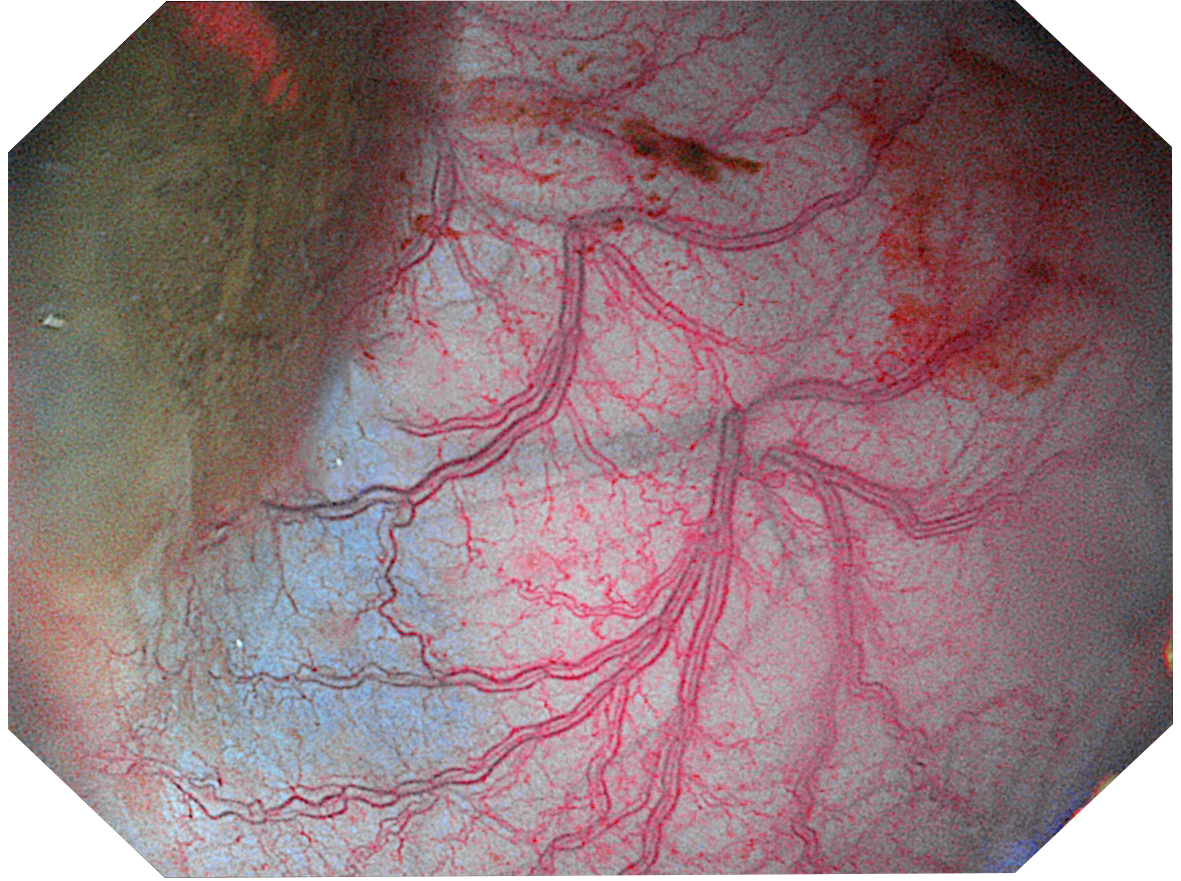

Три режима оптической хромоэндоскопии

Оснащен 4 светодиодными источниками света высокой яркости с независимым управлением, обеспечивающими многоспектральный режим окрашивания «белый свет + 3 спектра CBI». Спектральное окрашивание может повысить визуальный контраст между нормальной тканью и повреждениями, тем самым улучшая выявляемость небольших повреждений. Технология оптического окрашивания (CBI) – удобный и эффективный инструмент для выявления раннего рака, опухолевых и воспалительных процессов.

|  | CBI regular позволяет легко выявлять поражения слизистой оболочки и подчеркивать распределение подслизистых сосудов. |  |

|  | CBI indigo Усиливает контраст между слизистой оболочкой и кровеносными сосудами. |  |

|  | CBI aqua способствует лучшей визуализации структуры слизистой оболочки. |  |

Три режима оптической хромоэндоскопии (CBI). Многоспектральная визуализация с 4 светодиодами высокой яркости:

- CBI regular — визуализация слизистой и подслизистых сосудов.

- CBI indigo — усиление контраста между слизистой и сосудистой сетью.

- CBI aqua — улучшенное отображение структуры слизистой.